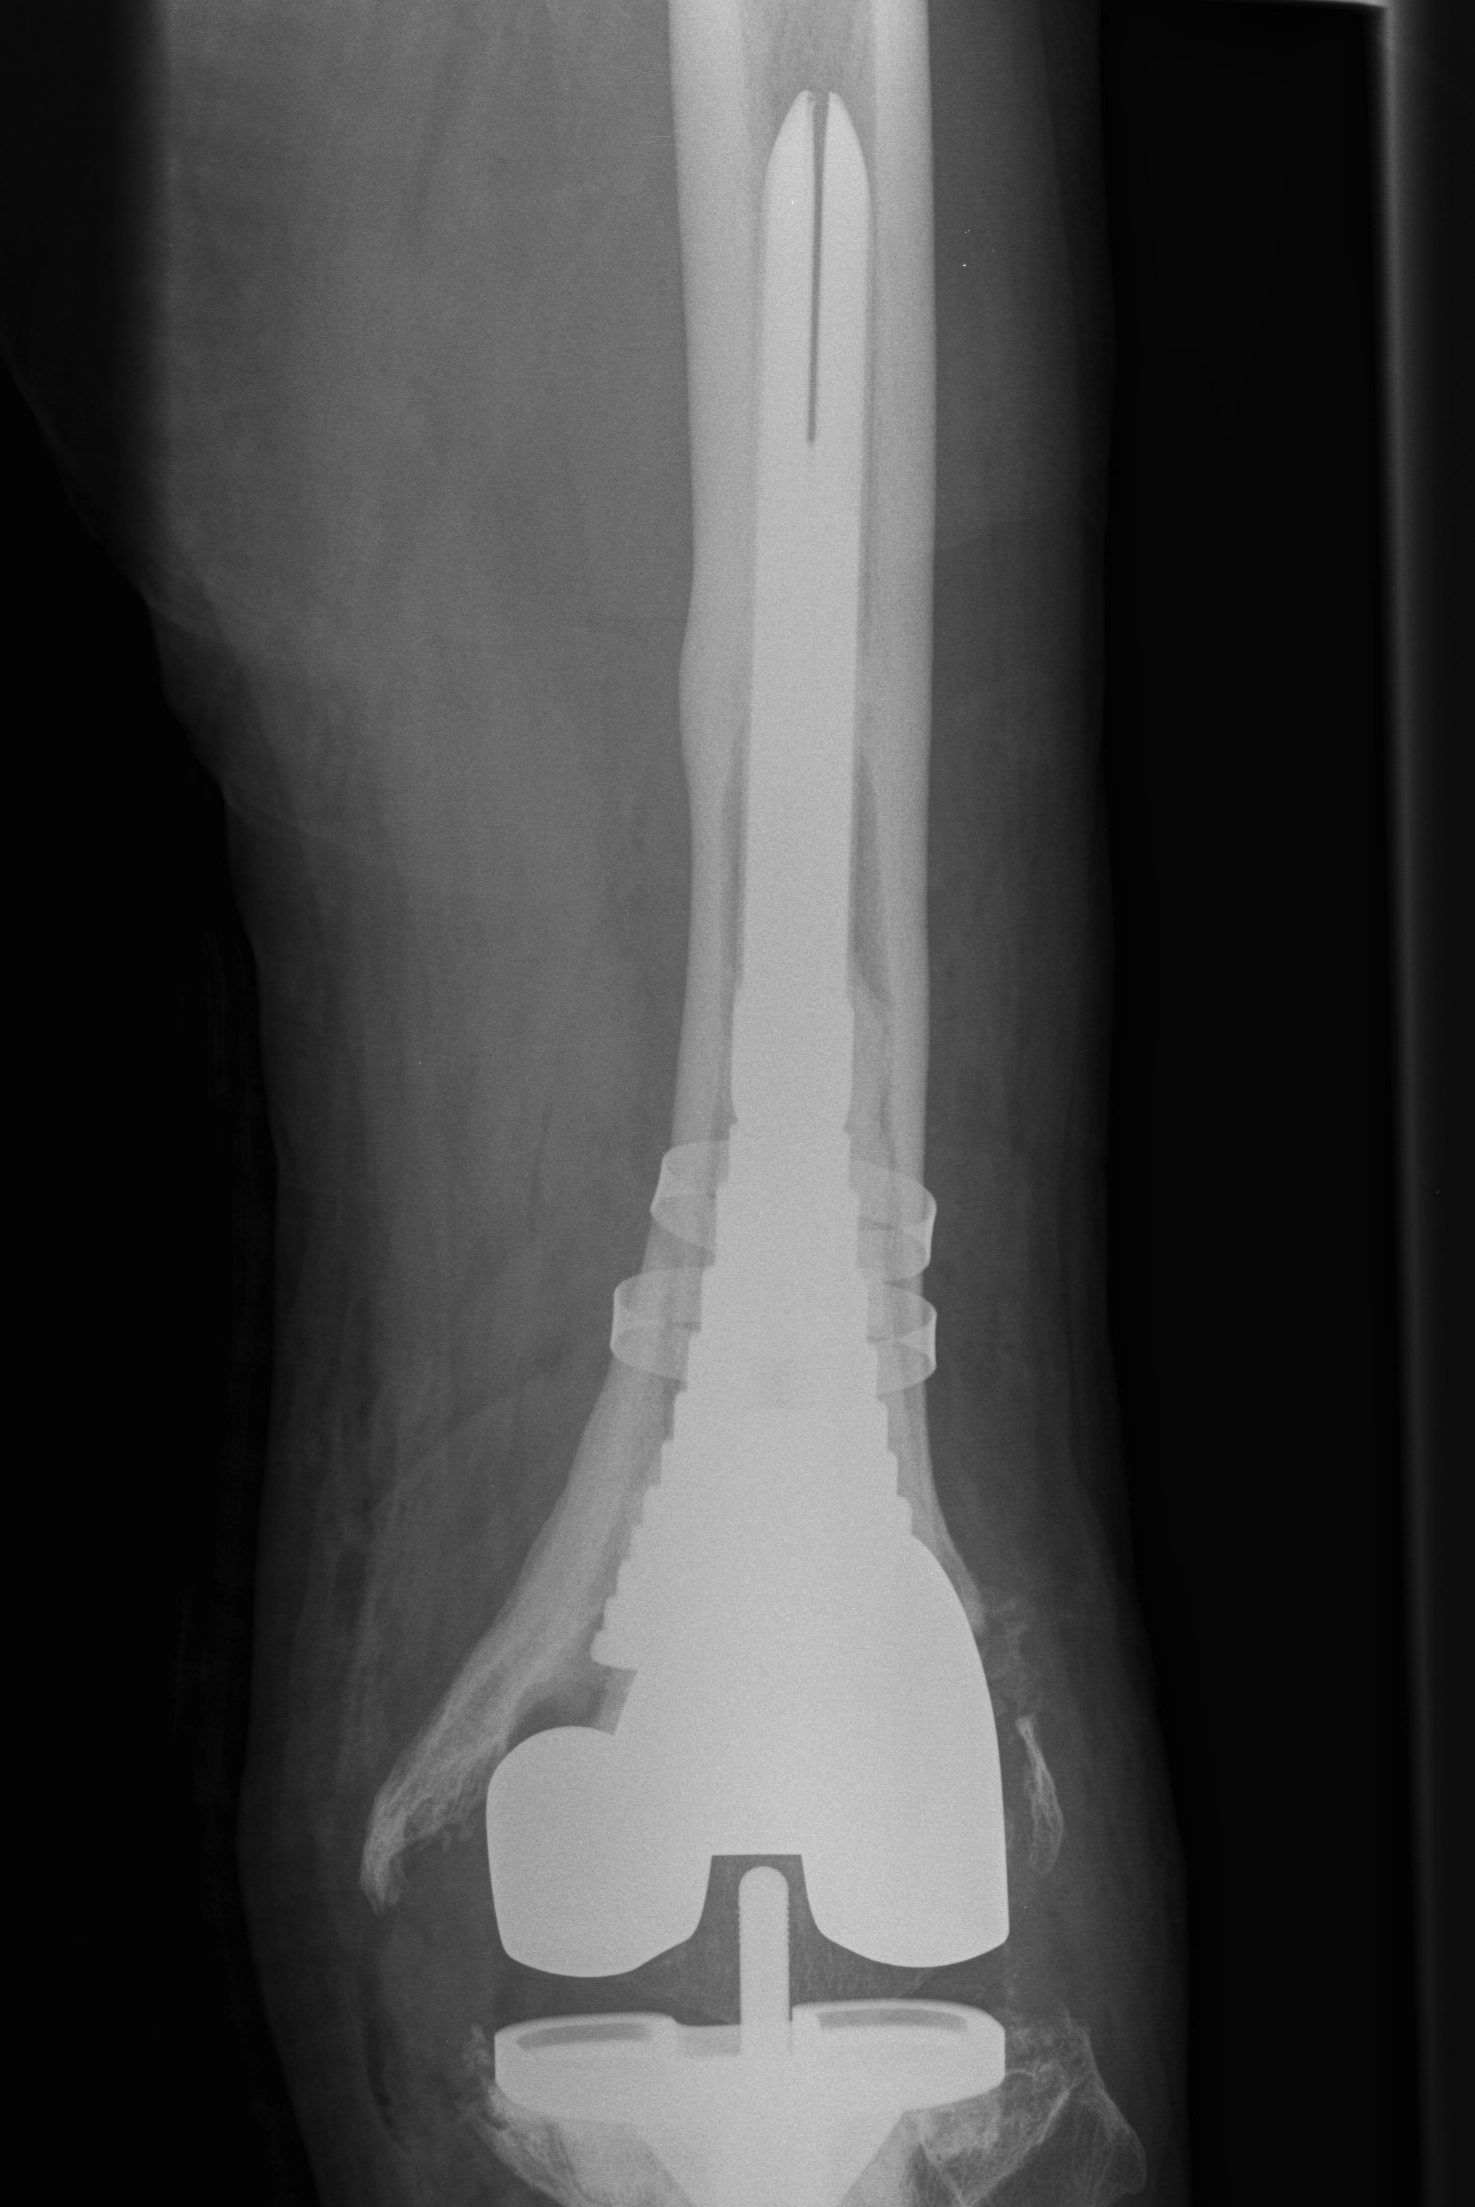

B. Tantalum cones metaphyseal filling / Trabecular metal

Meneghini et al JBJS Am 2009

- tantalum porous tibial implant in 15 pateints followed average 3 years

- AORI type 3 and type 2B

- knee society score average 85

- all had evidence osteointegration, no loosening